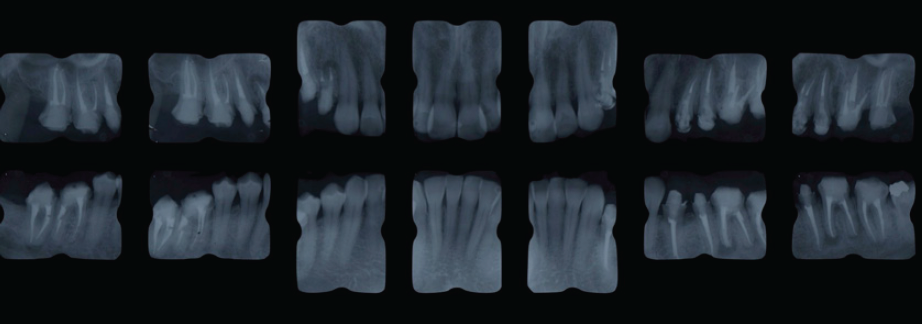

<緊急処置後、初期治療前の口腔内写真と14枚法>

歯周病の程度は軽度。前歯部開口咬合状態を呈し、

既往歴はほぼ臼歯部に集中している

口腔内の傾向から臼歯に過度な負担があり、

さまざまな病態に至っていると推測する

(図19-1)

(図19-2)

<臼歯部の感染根管治療終了後の14枚法>

(図20)

術前には数歯に根尖病変を疑う透過像が確認できたが

術後改善傾向にあることが確認できる